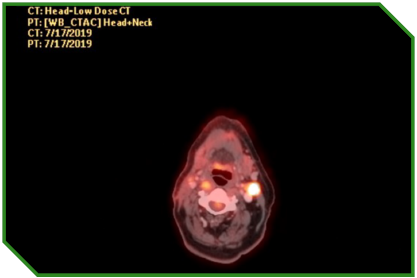

Paciente masculino de 72 anos, portador de carcinoma espinocelular de língua, tratado inicialmente com cirurgia e radioquimioterapia adjuvante, evoluindo com progressão linfonodal e pulmonar. Diante de comorbidades cardiovasculares e fragilidade clínica, recebeu quimioterapia paliativa, seguida da introdução de imunoterapia isolada, após confirmação de expressão tumoral de PD‑L1, permanecendo em acompanhamento clínico e radiológico após suspensão do tratamento por toxicidade imunomediada grave.